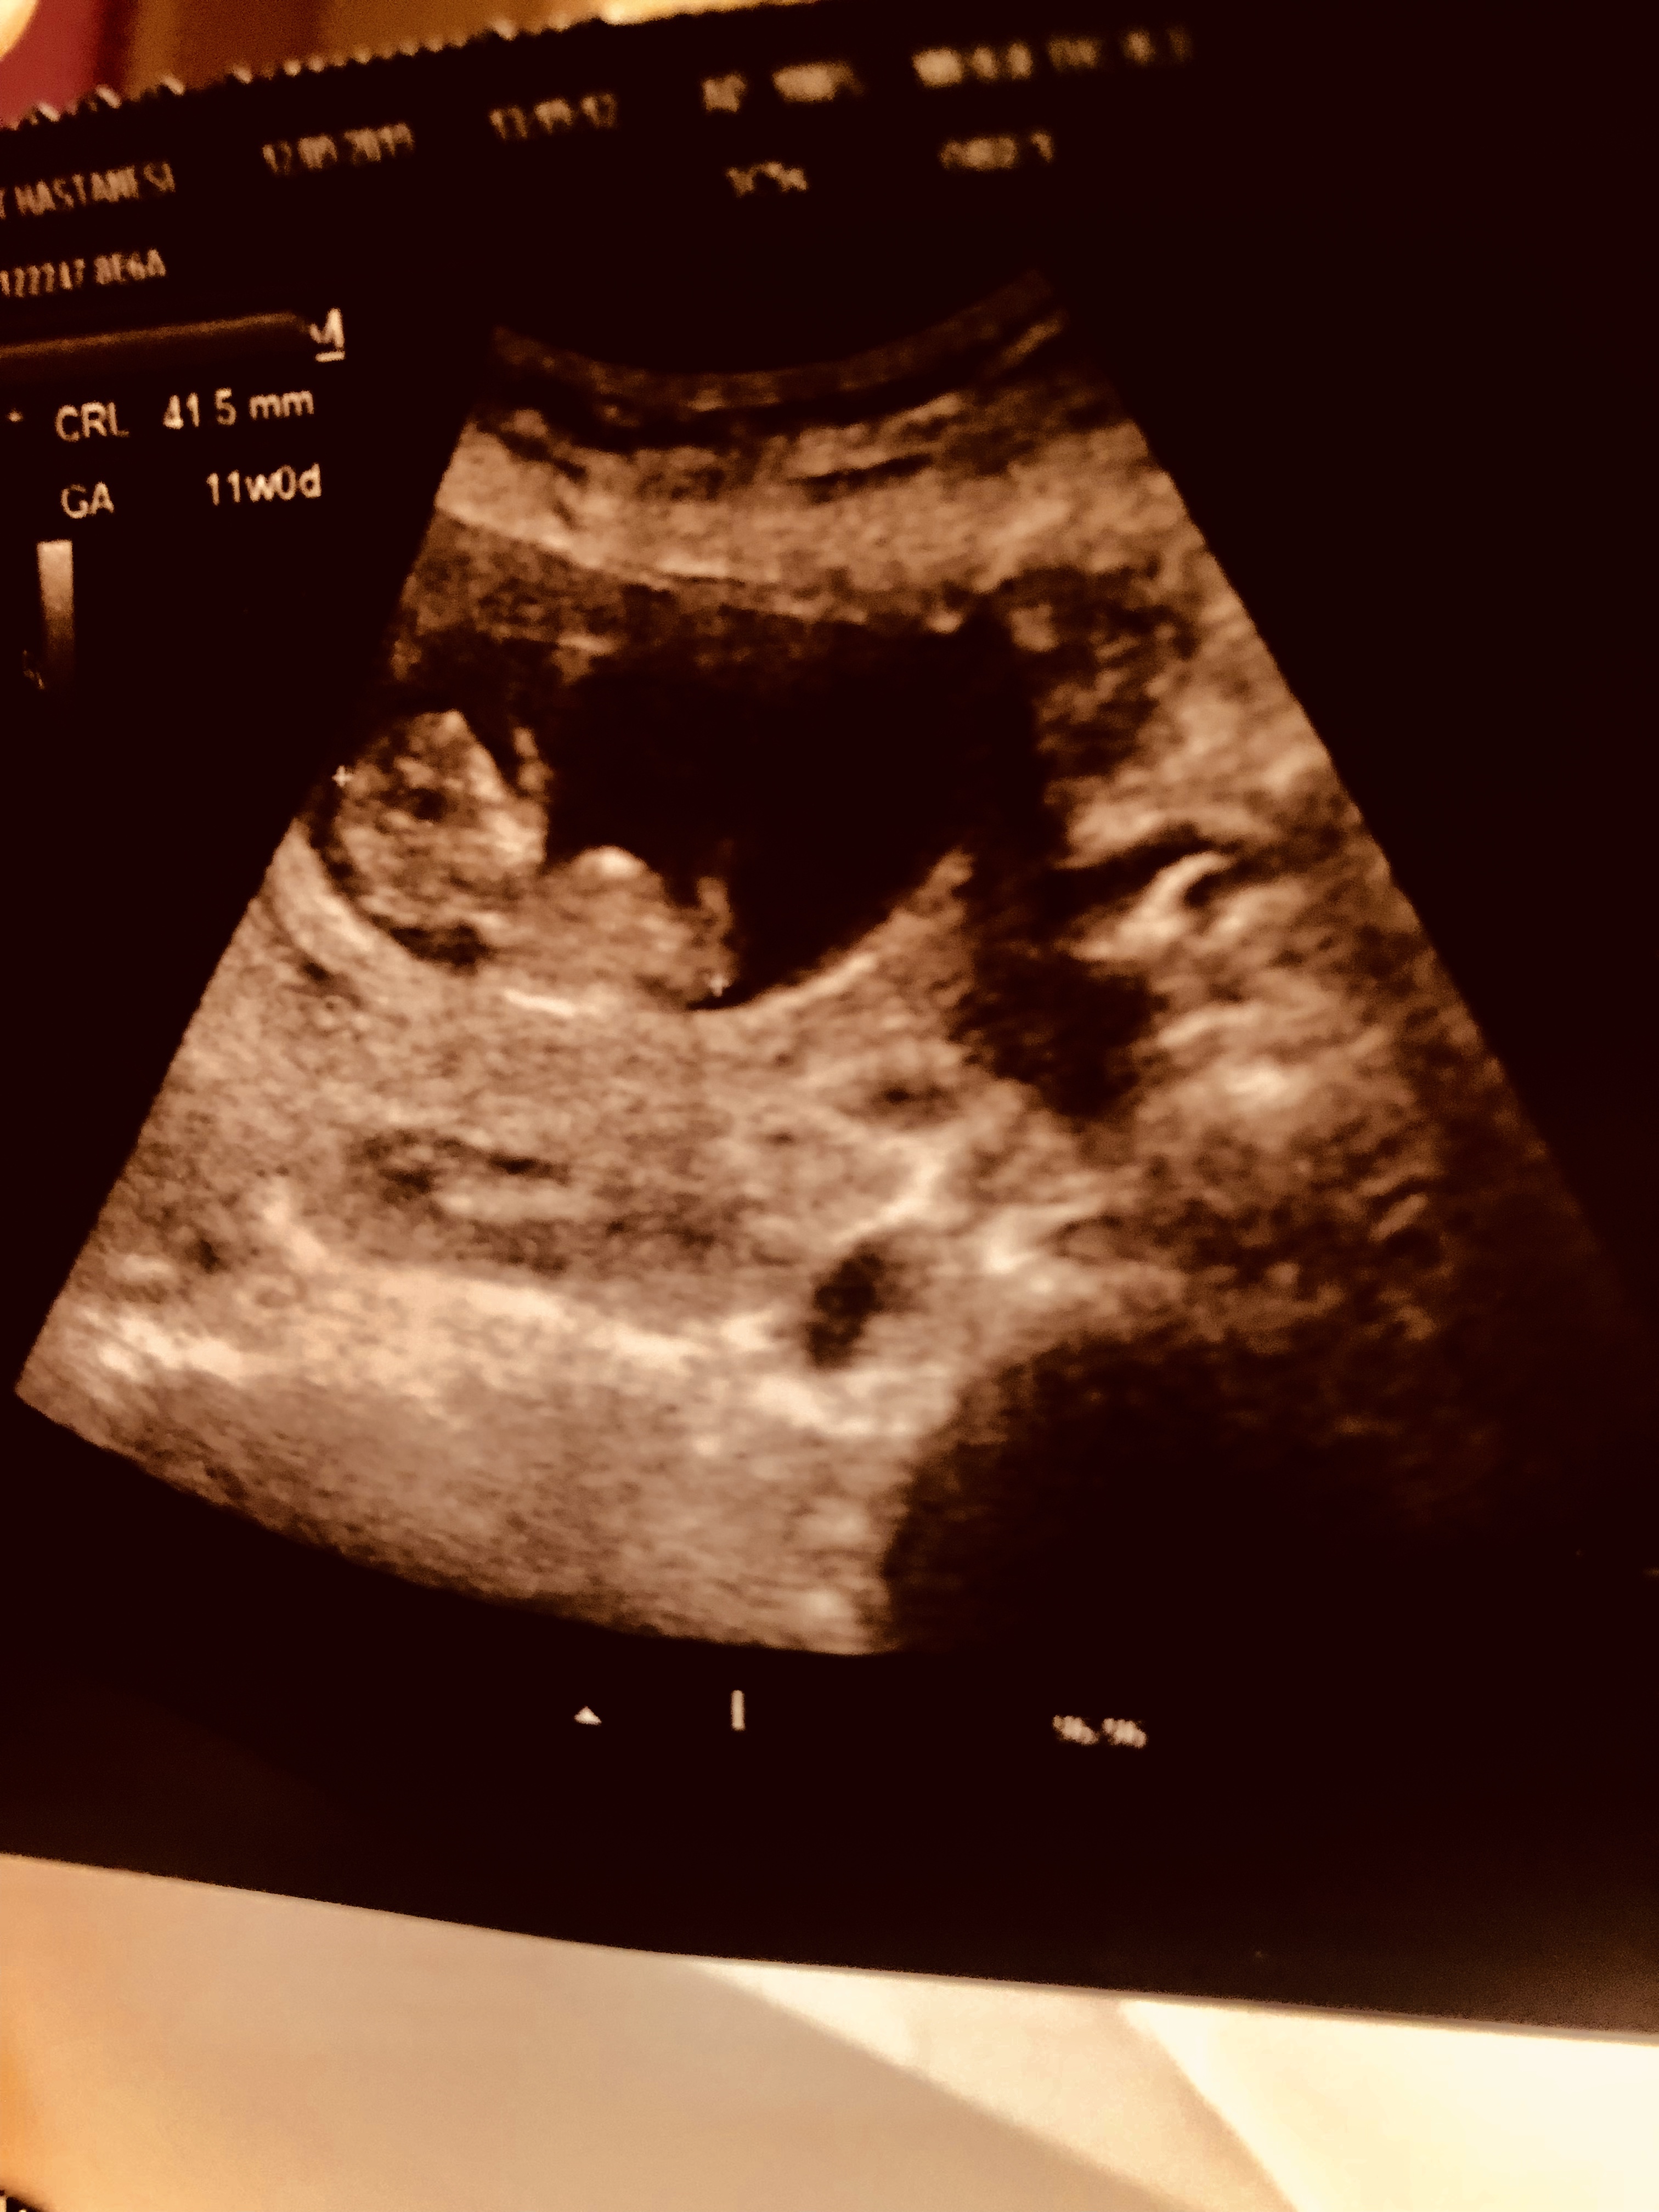

Bir tanesi 11 haftalık biri 13 haftalık tahmin yaparmışsınız